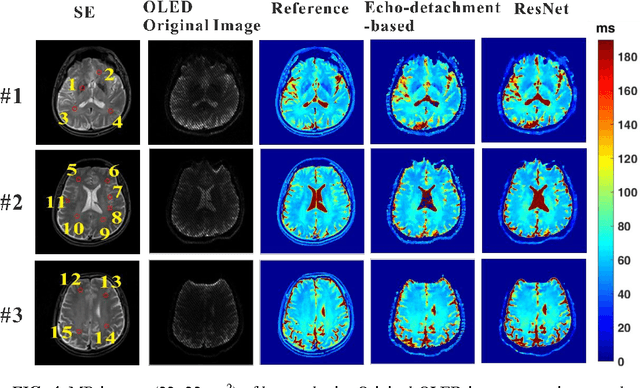

Abstract:Purpose: An end-to-end deep convolutional neural network (CNN) based on deep residual network (ResNet) was proposed to efficiently reconstruct reliable T2 mapping from single-shot OverLapping-Echo Detachment (OLED) planar imaging. Methods: The training dataset was obtained from simulations carried out on SPROM software developed by our group. The relationship between the original OLED image containing two echo signals and the corresponded T2 mapping was learned by ResNet training. After the ResNet was trained, it was applied to reconstruct the T2 mapping from simulation and in vivo human brain data. Results: Though the ResNet was trained entirely on simulated data, the trained network was generalized well to real human brain data. The results from simulation and in vivo human brain experiments show that the proposed method significantly outperformed the echo-detachment-based method. Reliable T2 mapping was achieved within tens of milliseconds after the network had been trained while the echo-detachment-based OLED reconstruction method took minutes. Conclusion: The proposed method will greatly facilitate real-time dynamic and quantitative MR imaging via OLED sequence, and ResNet has the potential to reconstruct images from complex MRI sequence efficiently.